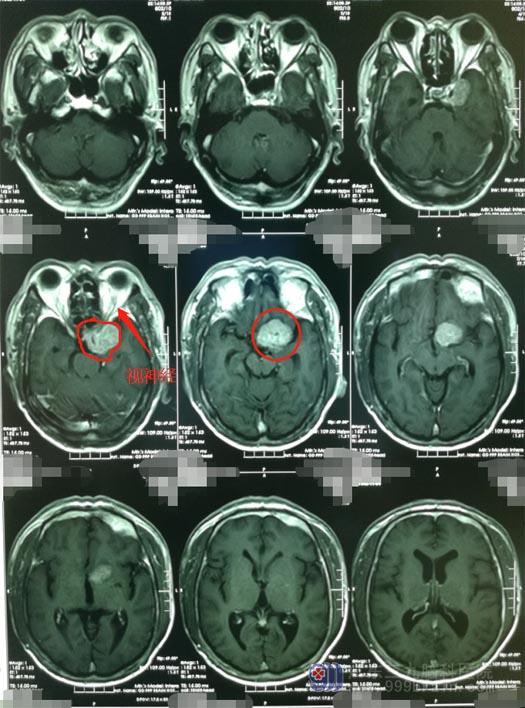

广东三九脑科医院的头颅MR检查显示:左侧蝶骨嵴占位性病变,大小约3.5cm×2.8cm×3.6cm,考虑脑膜瘤;头颅CTA提示:病灶内钙化灶,血供较丰富,病灶部分包绕左侧颈内动脉,压迫左侧大脑中动脉水平段向后移位。

▲术前MR